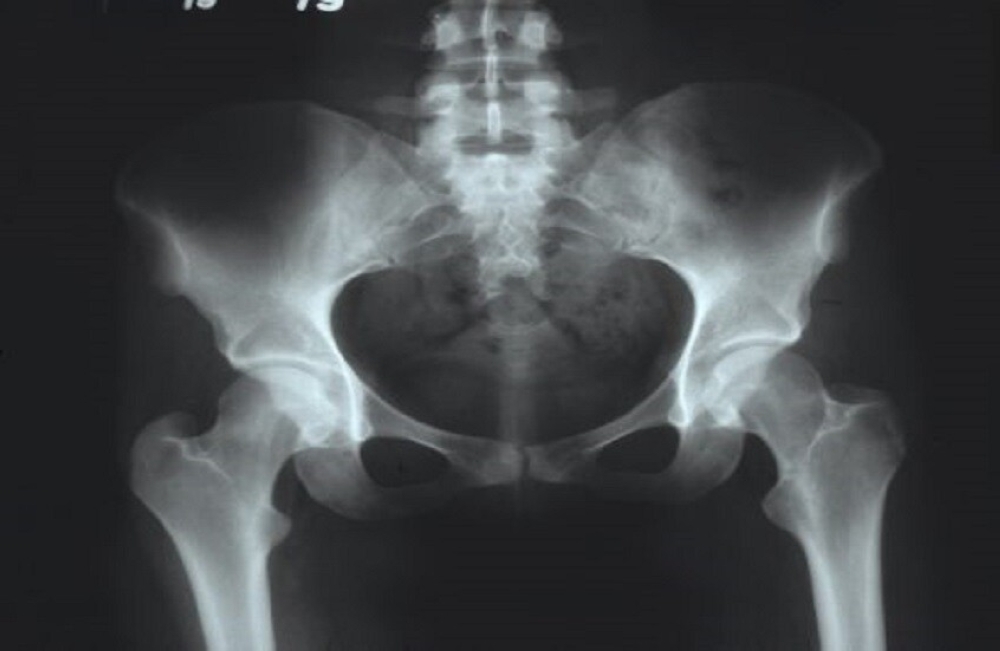

ووفقًا له، يُعدّ التهاب مفصل الورك أكثر أمراض مفصل الورك شيوعًا، وهناك العديد من الأسباب التي قد تؤدي إلى الإصابة به، مثل: التشوهات الخلقية، والتشوهات المكتسبة نتيجة الإصابات أو الأمراض المختلفة، والتغيرات التنكسية الناتجة عن التقدم في السن، والنشاط البدني المفرط، وزيادة الوزن، والاضطرابات الهرمونية.

ويشير إلى أن من الأعراض المميزة لالتهاب مفصل الورك الشعور بالألم أثناء الحركة وتقييد نطاقها؛ وفي المراحل المتقدمة، قد يُلاحظ قصر في الطرف السفلي، وغالبًا ما تكون العملية غير متماثلة، أي أنها تبدأ في أحد الجانبين أولا، ثم يتأثر الطرف الآخر نتيجة التحميل الزائد على المفصل السليم، وتُعدّ الفئة الأكثر عرضة للإصابة بالمرض هي الأشخاص الذين تزيد أعمارهم على 50 عامًا، وتُعدّ النساء أكثر عرضة للإصابة من الرجال.